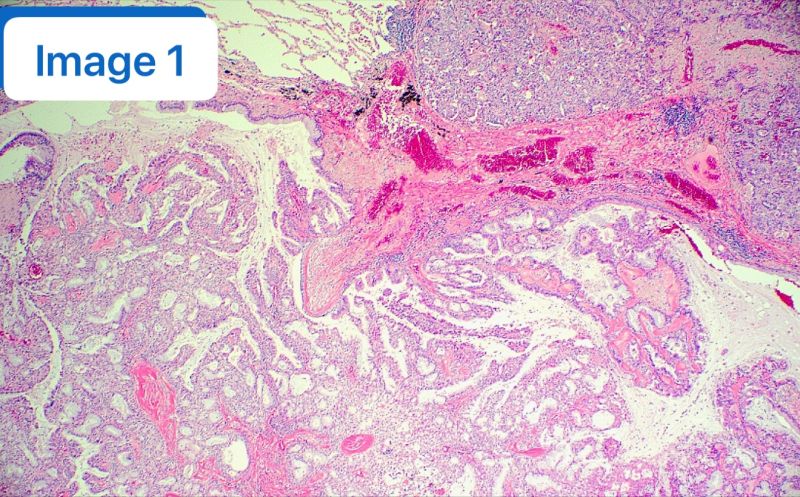

🔪 【反转与真相】 患者随后接受了手术切除,但大体标本的切片却讲述了一个完全不同的故事。 显微镜下呈现出了 CMPT 的经典特征(见附图):

- 明显的乳头状和腺样结构(图1);